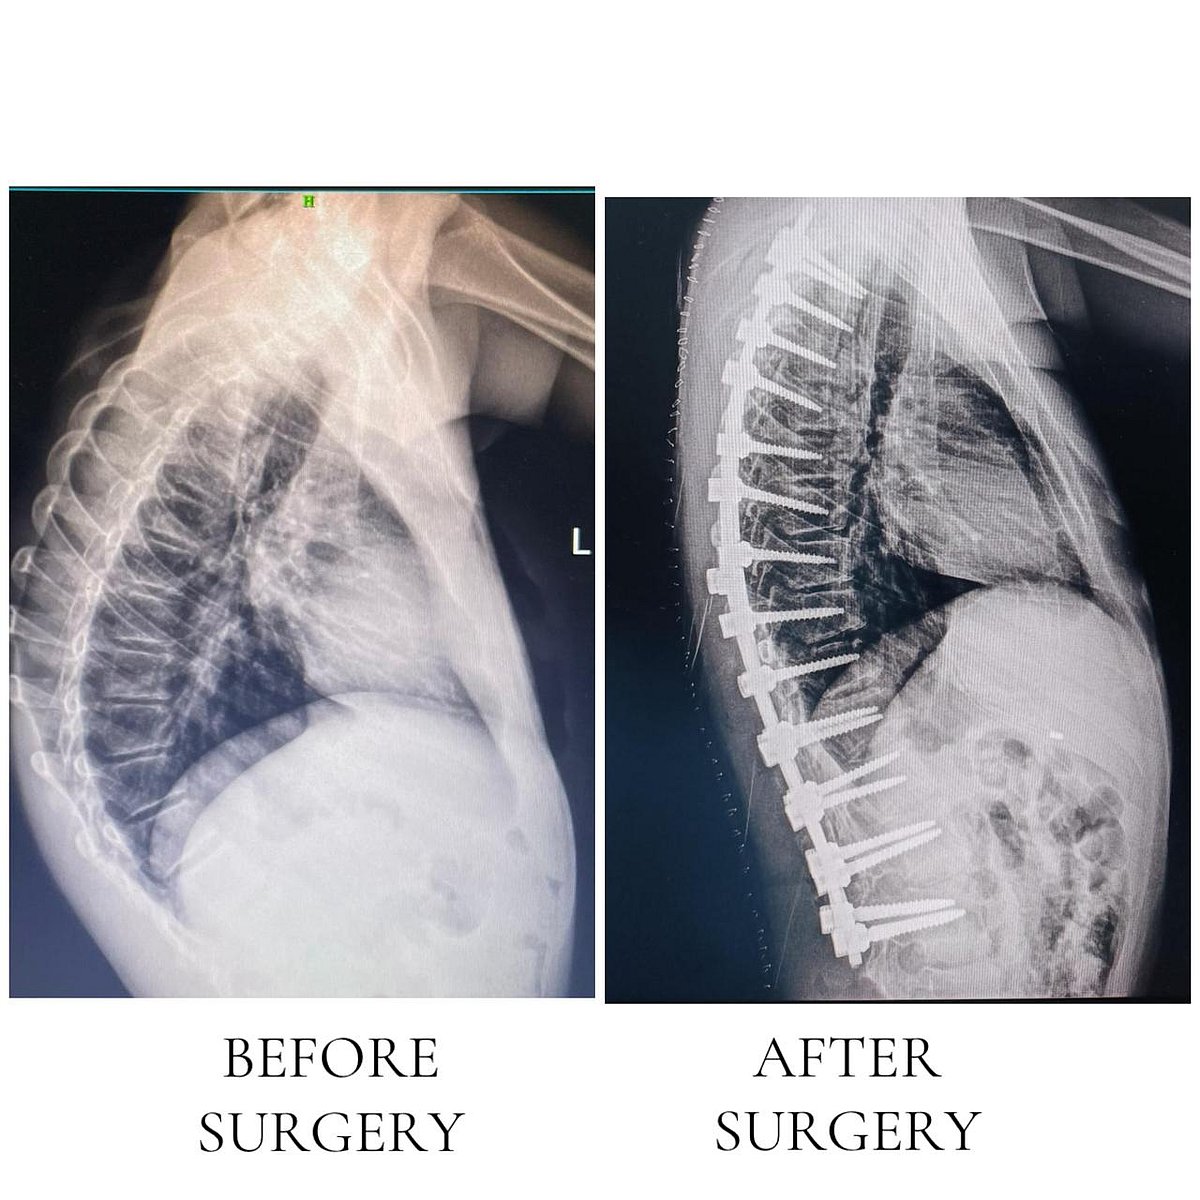

According to senior doctors, the patients — 24-year-old Divya Suryawanshi from Dhule and 15-year-old Master Rasul Shaikh from Nizamabad — had been living with progressive spinal kyphoscoliosis, a condition that severely impacts posture, mobility, and lung capacity.

For the first time in the state, surgeons used the cutting-edge Mazor X Spine Robot with O-arm navigation, which allows for highly accurate screw placement and real-time 3D imaging during surgery.

“The robotic system enables exceptional precision, reduces surgical risks, and facilitates faster recovery for patients with complex spinal deformities,” explained Dr Nadir Shah, Head of the Orthopaedics Department.